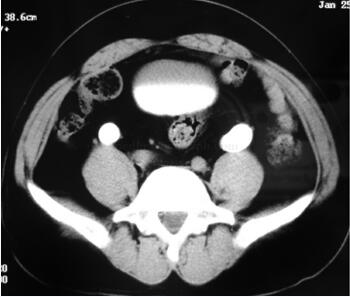

膀胱造影:膀胱拉长,明显上移(图46-1)。

图46-1 膀胱造影